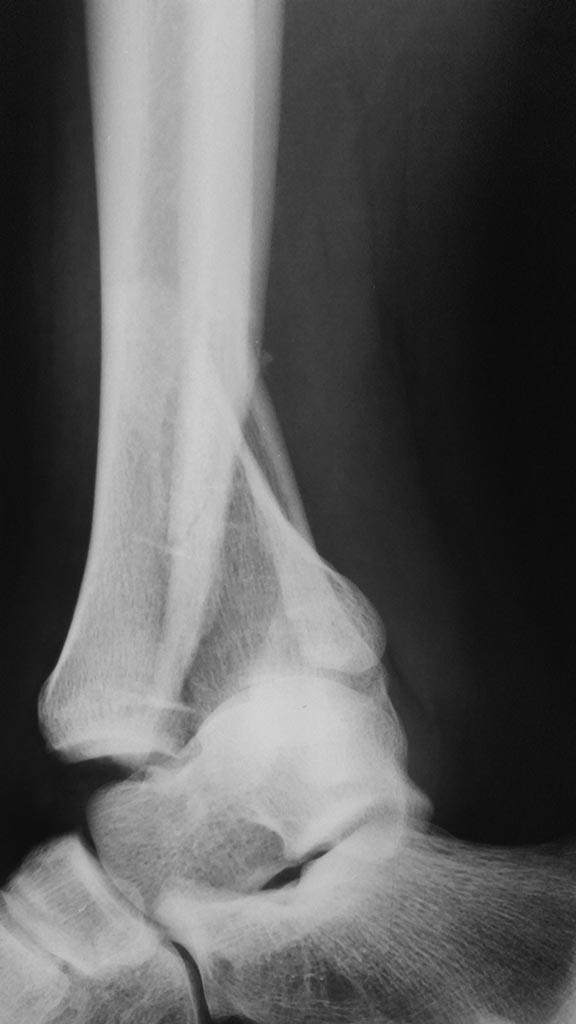

Оскольчатый внутрисуставной перелом костей голени

Пациент 24 года с внутрисуставным оскольчатым переломом дистального метаэпифиза большеберцовой кости, оскольчатым перелом нижней трети малоберцовой кости со смещением отломков.